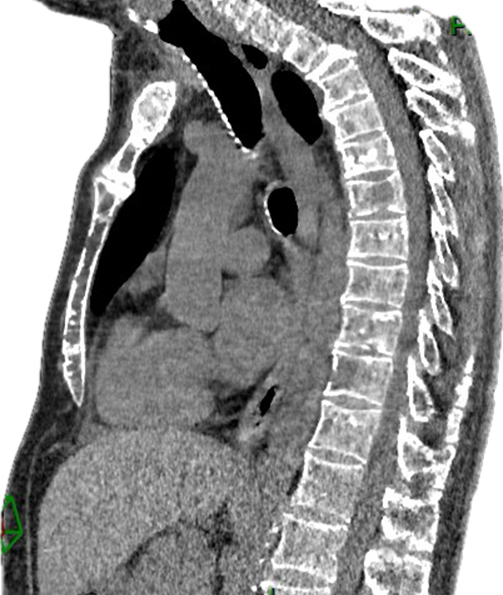

Vous recevez un soir aux urgences Mme D., 67 ans, pour une douleur basithoracique bilatérale.

Elle n’a pas d’antécédent en dehors d’une pneumonie récidivante depuis trois mois.

La douleur dure depuis plusieurs jours, d’intensité progressivement croissante, actuellement à 9/10 malgré des antalgiques de palier 1. Elle ne rapporte pas d’élément déclencheur.

Les paramètres vitaux sont les suivants : pression artérielle (PA) = 123/76 mmHg ; fréquence cardiaque (FC) = 99 bpm ; saturation en oxygène (SpO2) = 97 % en air ambiant ; température (T°) = 37,1 °C.

L’examen clinique cardiopulmonaire est normal. L’électrocardiogramme (ECG) montre une tachycardie sinusale.